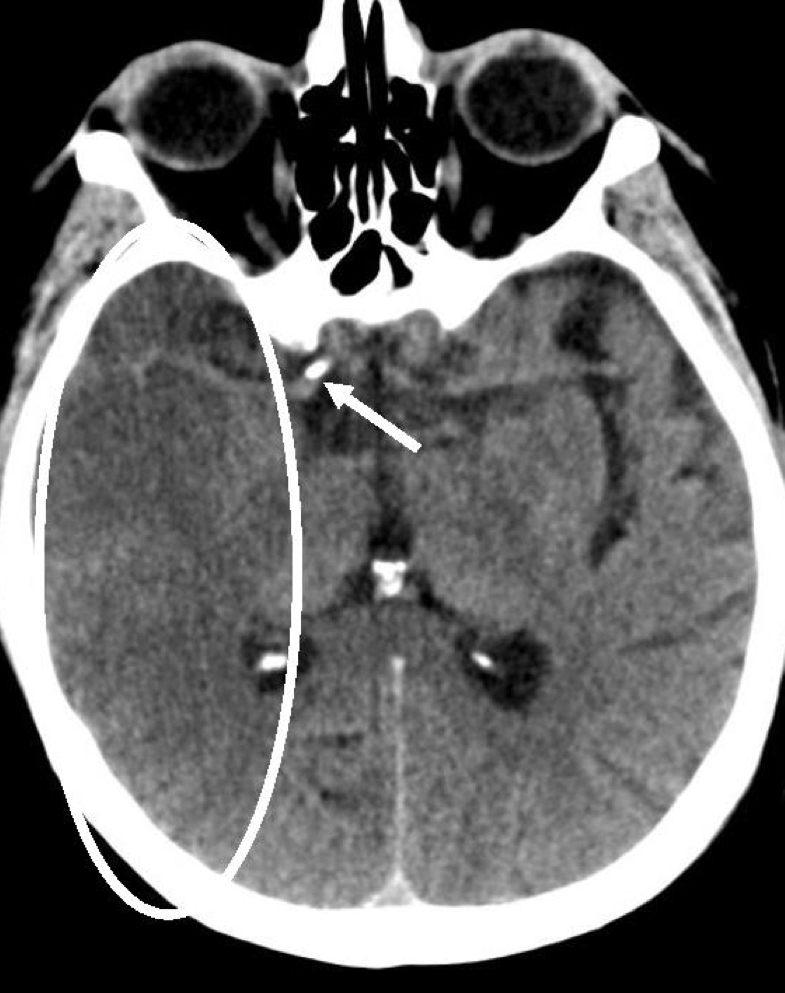

14

Q

Que signo ves aqui?

A

RM de evc Hemorragico

Signo de “Falso realce”

se ve poligono de willis

sin contraste